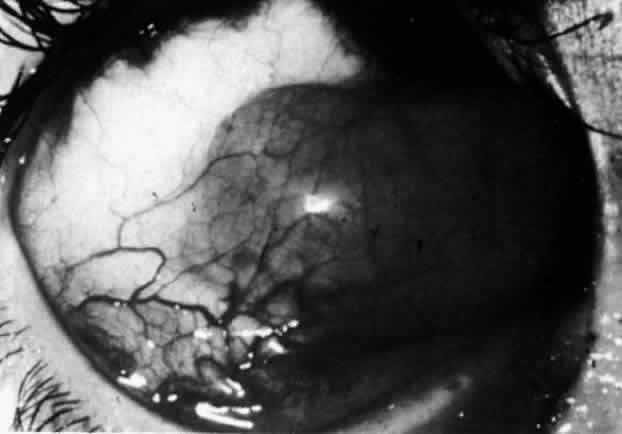

Fig. 42. Late arterial phase of fluorescein angiogram in a patient with necrotizing

scleritis. All the vessels except the main trunk and the vessels around

the limbal perforating vessels are occluded and remain unperfused

throughout the angiogram. Fig. 42. Late arterial phase of fluorescein angiogram in a patient with necrotizing

scleritis. All the vessels except the main trunk and the vessels around

the limbal perforating vessels are occluded and remain unperfused

throughout the angiogram.

|